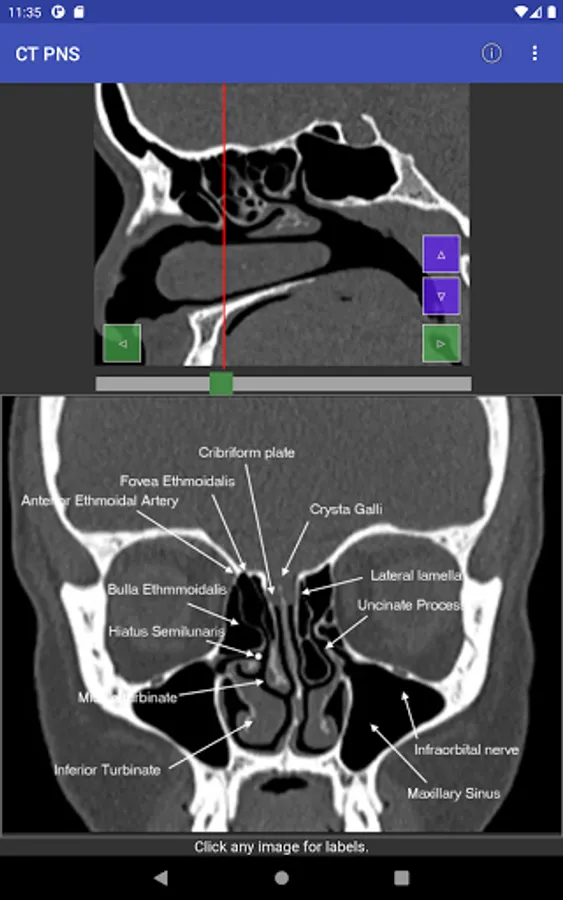

For easy of understanding CT scan anatomy, the content is correlated in two planes, with one serving as a reference. Hence it is much easier to understand the anatomy as we face in the clinical situation. Both the planes can be individually scrolled, so depth is easier to understand.